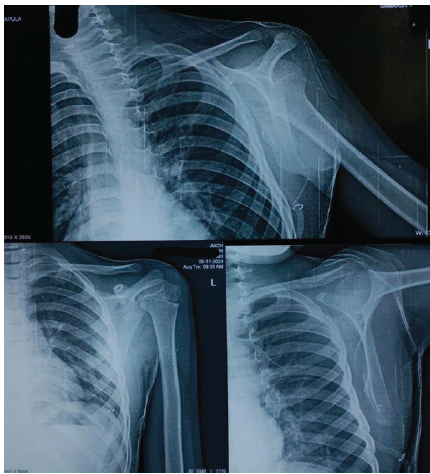

Histopathology confirmed the diagnosis of a benign osteochondroma with no evidence of malignant transformation. At 6-week follow-up, the surgical wound had healed satisfactorily, with restoration of scapular contour and significant improvement in shoulder range of motion. Post-operative radiographs confirmed complete excision of the lesion (Fig. 5), and clinical evaluation at 6 weeks showed restoration of scapular contour (Fig. 6), the patient returned to routine activities without restriction.

Figure 5: Immediate post-operative shoulder radiograph. Immediate post-operative radiograph of the left shoulder in anteroposterior view, obtained following surgical excision, confirming complete removal of the scapular lesion with restoration of normal scapular contour.